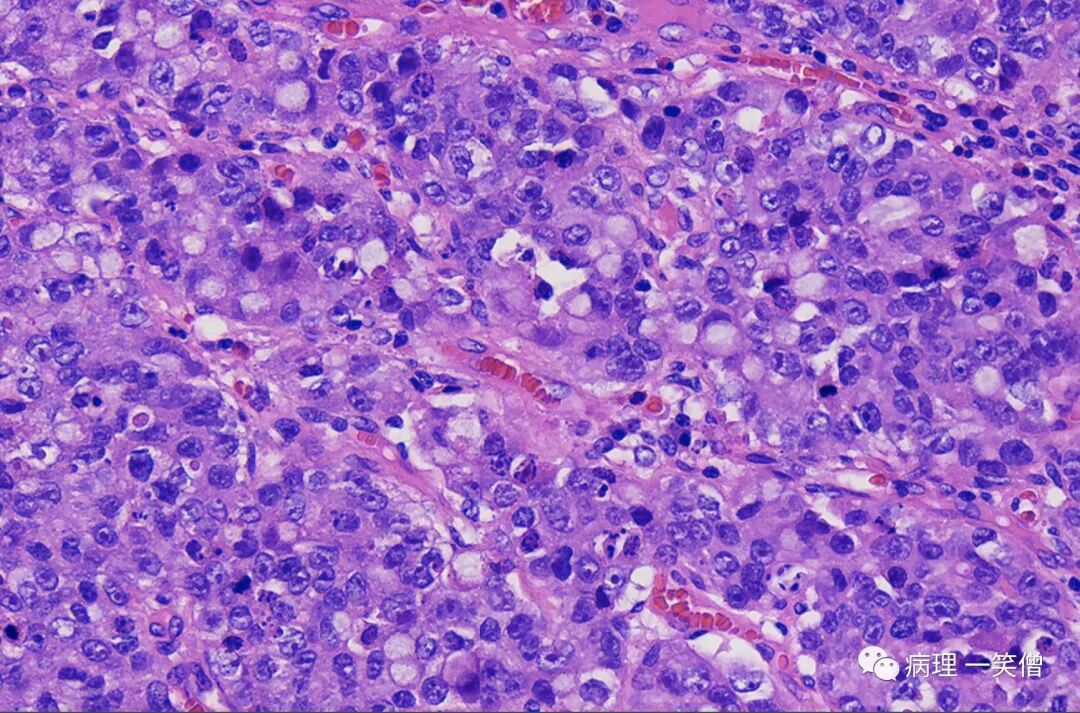

模式1:肿瘤细胞呈明显的巢团状排列伴间质胶原纤维增生,巢周细胞呈栅栏状结构;巢团内肿瘤细胞胞质丰富,部分充满细胞内黏液,部分为嗜伊红粉染颗粒,其中黏液样细胞多位于肿瘤巢中央,富含颗粒的细胞多位于巢团周边;细胞核呈卵圆形或不规则形,核分 裂象多见。

模式 2:肿瘤细胞呈弥漫性分布;细胞呈圆形或不规则形,可见中等量细胞质,呈黏液样,部分肿瘤细胞胞质嗜伊红色;细胞核不规则形,染色质较细腻,核分裂象多见。

模式3:肿瘤细胞呈不规则腺管状或筛状分布伴菊形团样结构;细胞质可见嗜伊红颗粒或多量黏液;核染色质较细腻,核分裂象多见。